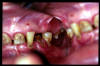

CM Enfermedad periodontal avanzada